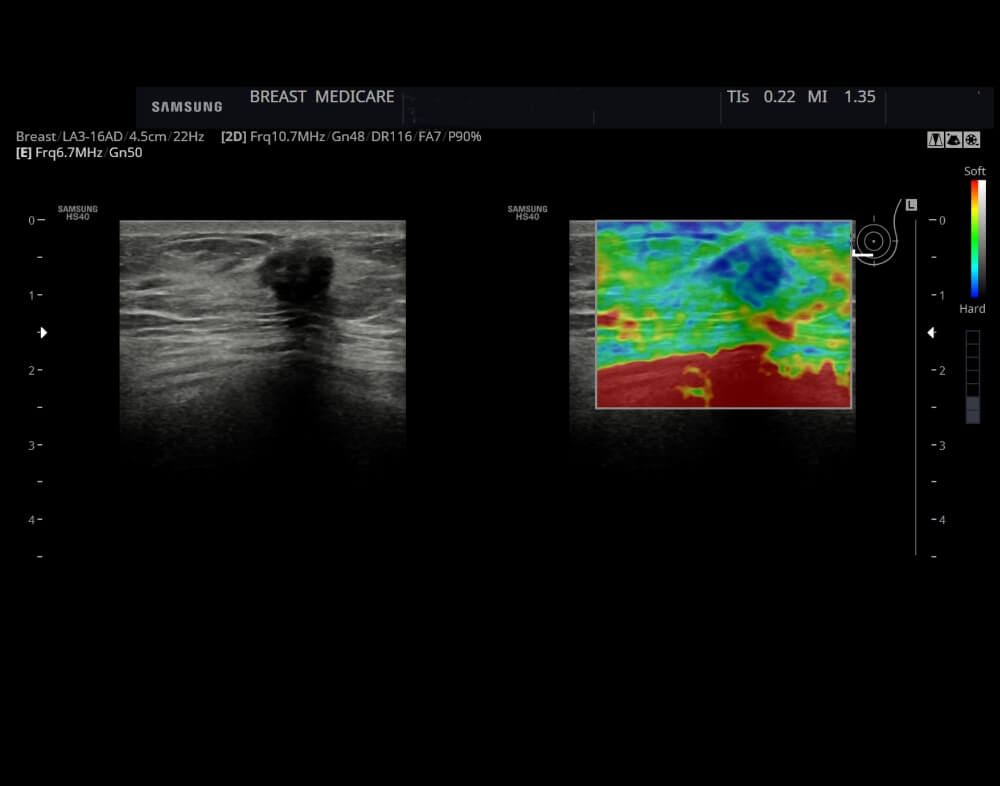

Στην μαστογραφία και στο υπερηχογράφημα μιμείται εικόνα καρκινώματος του μαστού.